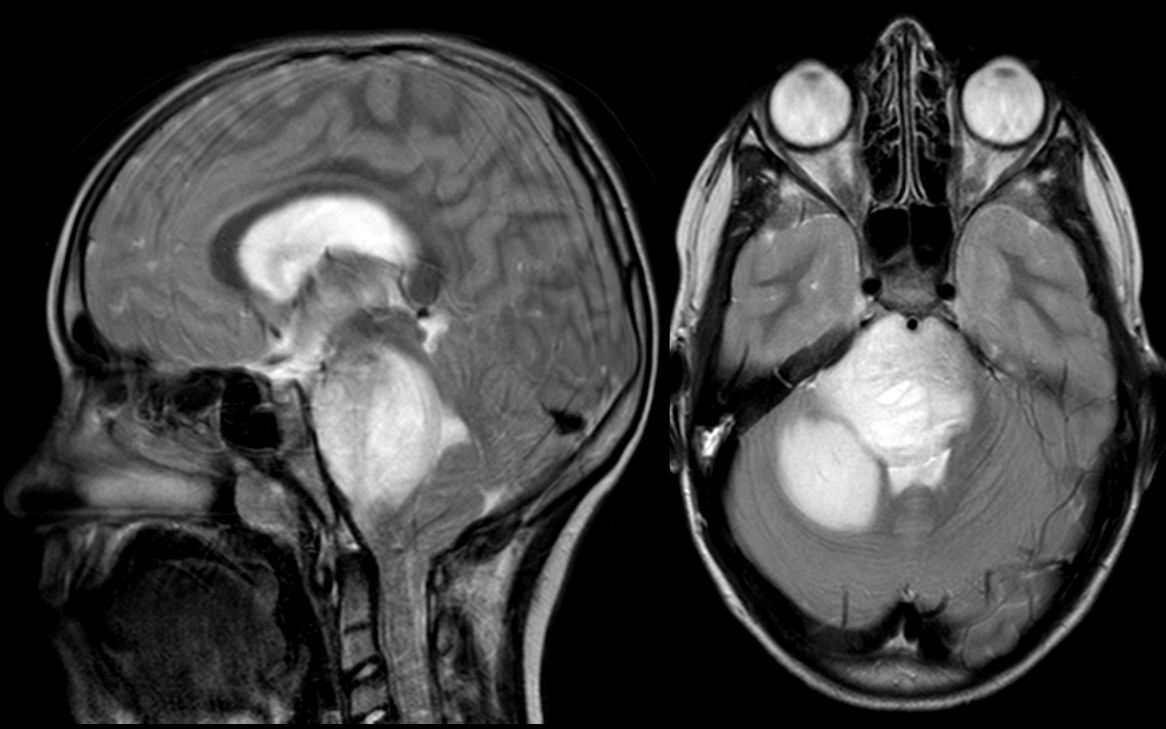

Diffuse midline glioma, a rare tumor that typically occurs in young children and is fatal within a year. Credit: Great Ormond Street Hospital, London, United Kingdom